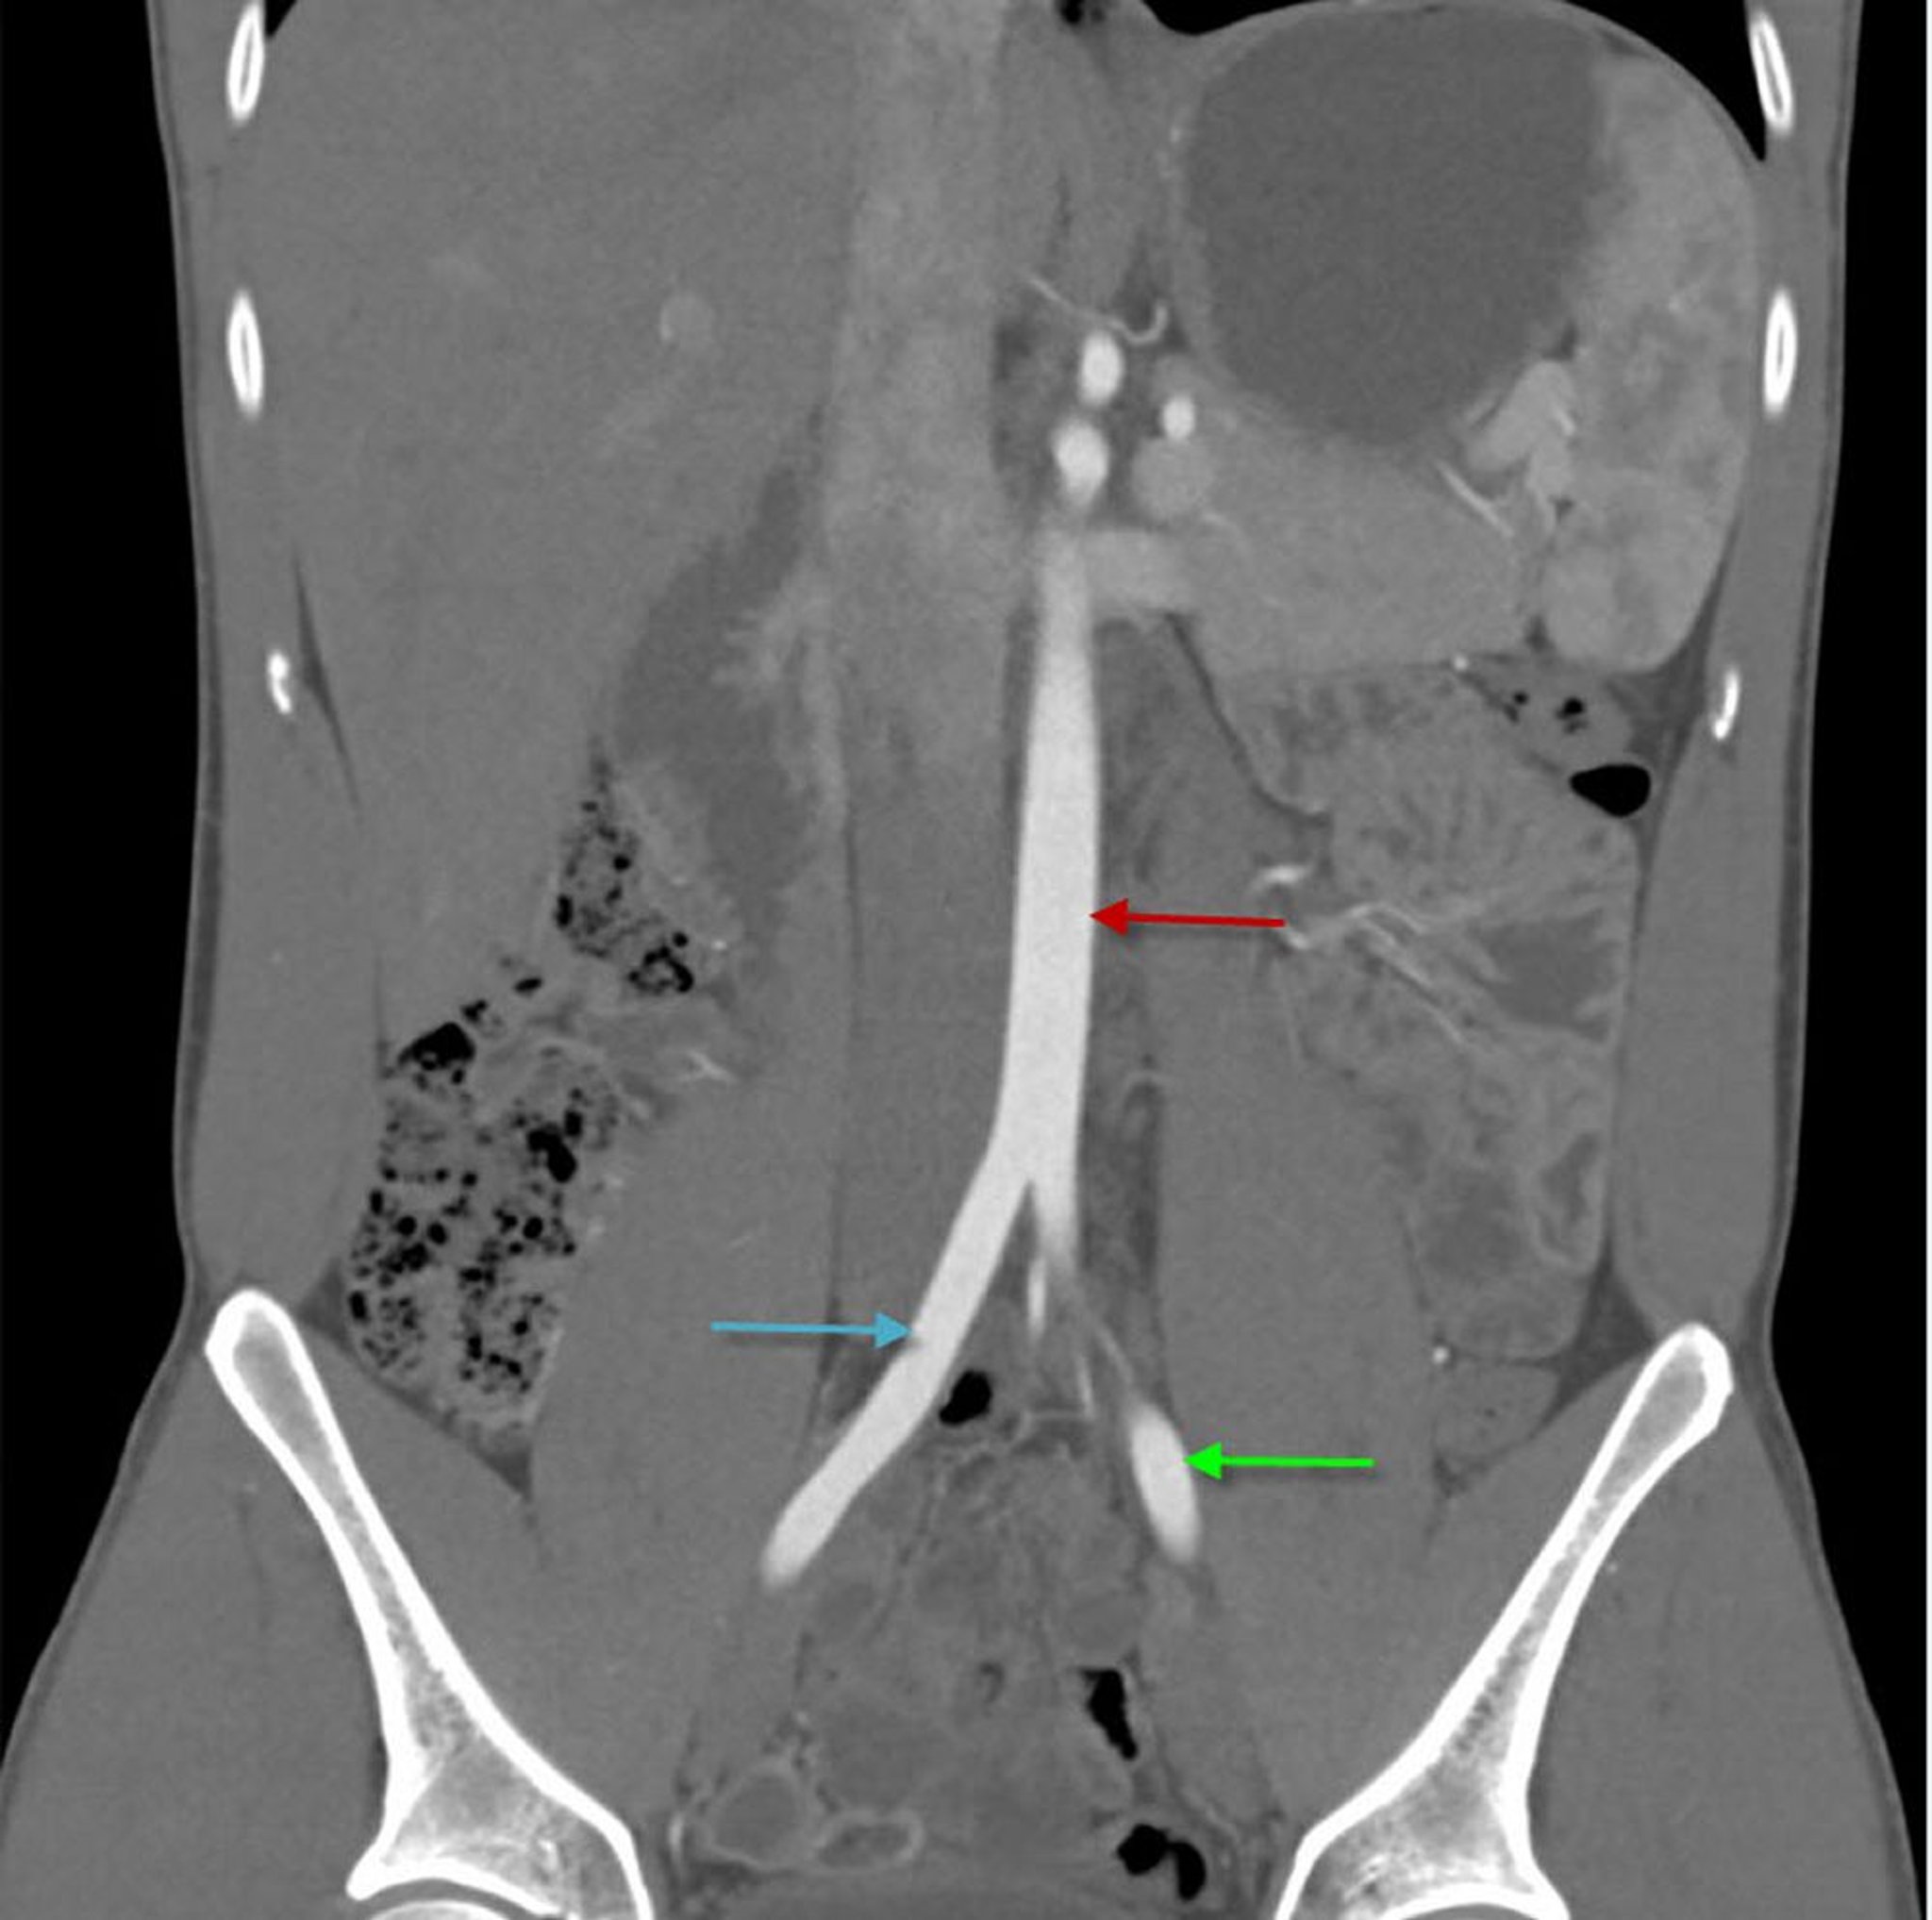

CTA (khung hình đứng ngang) của bụng cho thấy động mạch chủ bụng

Hình ảnh này cho thấy động mạch chủ bụng (mũi tên màu đỏ) chia thành động mạch chậu chung phải (mũi tên màu xanh làm) và trái (mũi tên màu xanh lá cây).